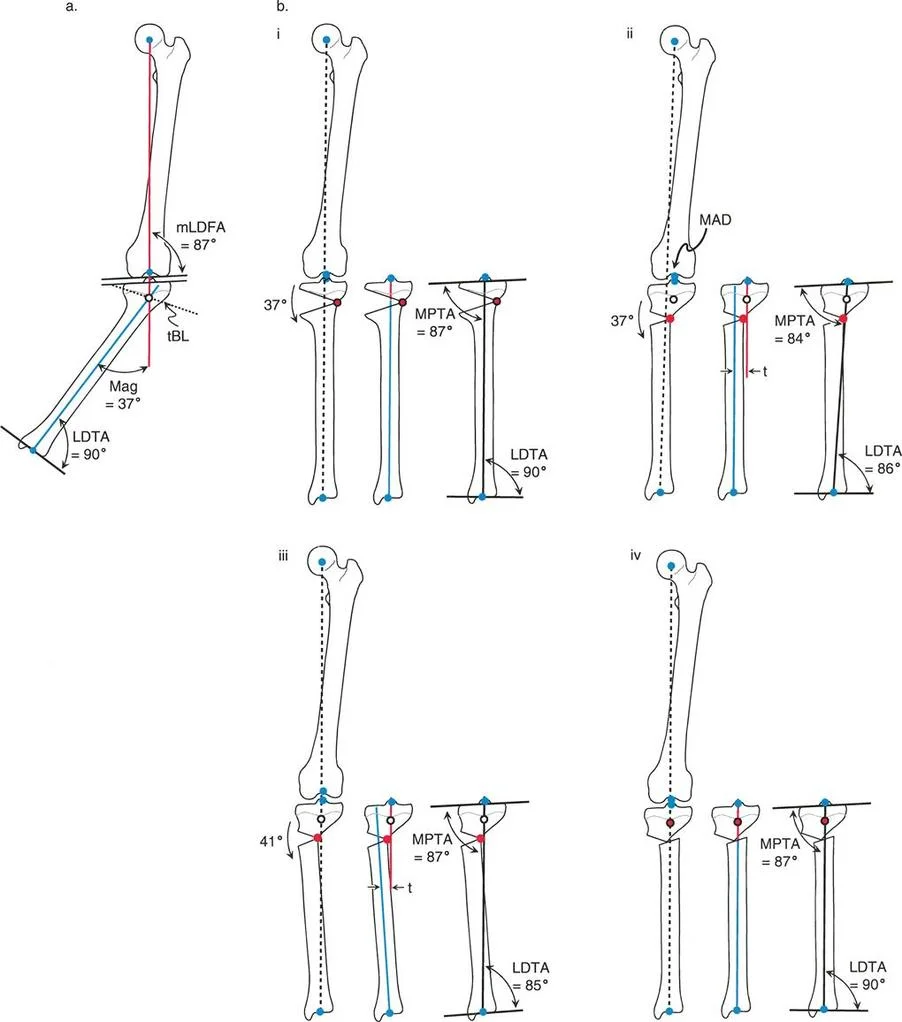

إن نجاح جراحة تصحيح تشوهات الأطراف يعتمد بشكل كبير على التخطيط المسبق الدقيق. هذا التخطيط أشبه برسم خارطة طريق هندسية تضمن أن كل خطوة جراحية تقود إلى النتيجة المرجوة. يعتمد هذا التخطيط على "مبادئ بالي" التي تحدد ثلاثة متغيرات هندسية أساسية في كل حالة:

- مركز دوران التشوه (CORA - Center of Rotation of Angulation): هذه هي النقطة المحورية للتشوه في العظم. يحددها الجراح من خلال رسم محاور الطرف قبل الجراحة.

- محور تصحيح الزاوية (ACA - Angulation Correction Axis): هذه هي النقطة التي يدور حولها الجزء البعيد من العظم لتصحيح التشوه. يتحكم الجراح في هذه النقطة عن طريق وضع المفصلات على المثبت الخارجي أو نقطة الارتكاز للوحة التثبيت.

- مستوى قطع العظم (Osteotomy Level): هذا هو الموقع الفعلي الذي يتم فيه قطع العظم. يتحكم الجراح بشكل كامل في هذا المتغير، ويتم اختياره بناءً على عوامل مثل الأنسجة الرخوة، وجودة العظم، ونوع الأجهزة المستخدمة.

النتيجة النهائية للتصحيح تعتمد كليًا على كيفية ارتباط هذه المتغيرات الثلاثة ببعضها البعض. الفشل في التخطيط الدقيق يمكن أن يؤدي إلى "تشوهات ثانوية" غير مرغوب فيها، مثل انحراف المحور الميكانيكي أو ترجمة (إزاحة) العظم.